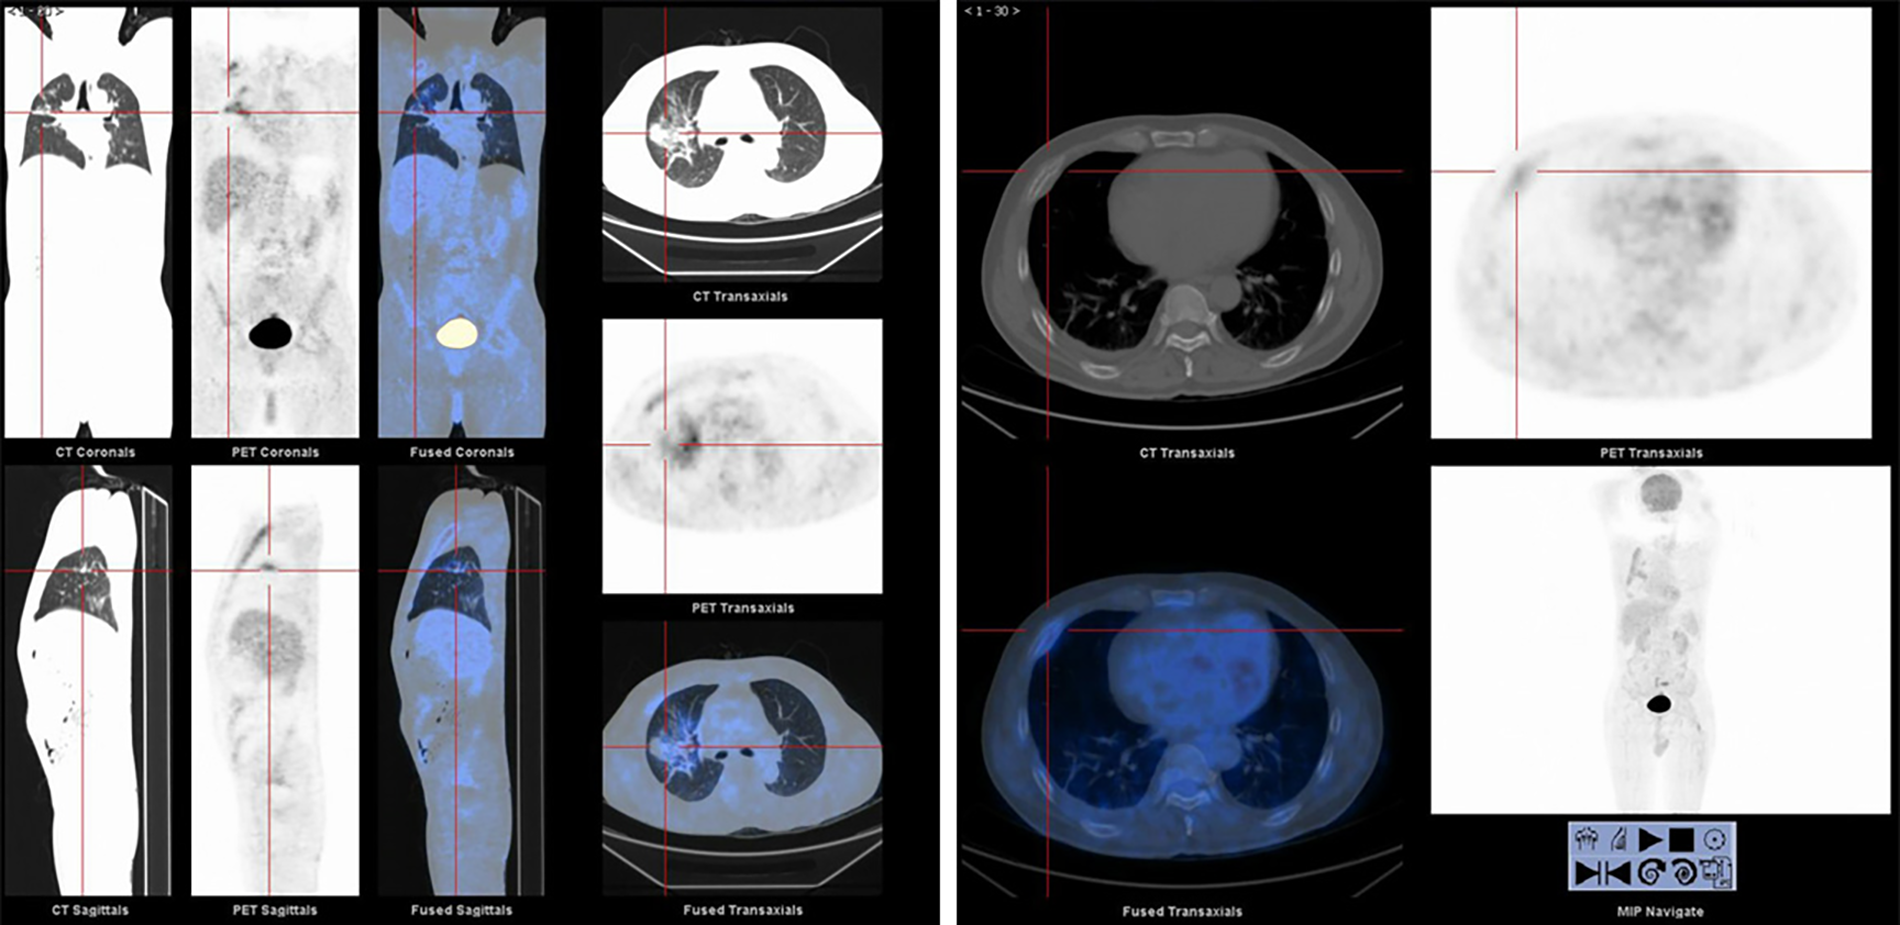

Once admitted to the tumor ward, the patient first underwent Positron Emission-Computed Tomography (PET-CT) which showed that the metabolism of the anterior part of the right 4th rib was abnormally increased and the nodules and clumps of the upper lobe of the right lung had increased metabolism (Figure 2). On the second day of admission to the tumor ward, the patient developed numbness in both lower extremities. At this point in time, examination showed that the patient had a right lower limb muscle strength of grade II and left lower limb muscle strength of grade III, accompanied by weakened sensation. Based on this observation, the patient was diagnosed with a high possibility of bone metastasis from primary lung cancer, accompanied by spinal cord compression, with poor prognosis and a very short survival time. The patient was given palliative treatment, and MRI examinations of the thoracolumbar vertebrae and pelvis were considered. On the fourth day of admission to the tumor ward, the patient developed paraplegia of the lower limbs bilaterally with grade 0 muscle strength, and rib tenderness in the right anterior chest. After evaluation, the doctors found that the lesions in the high metabolic site of the patient’s lungs were too close to large blood vessels of the lungs, hence high risk of vessel injury and massive bleeding related to puncture prevented a possible biopsy. After optimization of the radiotherapy plan the patient underwent radiotherapy for the thoracic (T3–4) and lumbar (L6–8) vertebrae.

FIGURE 2

www.frontiersin.org

Figure 2. PET-CT images of primary mucinous lung adenocarcinoma with rib metastases.